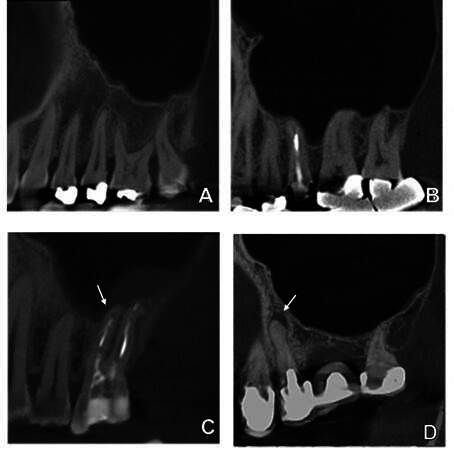

本研究旨在通过对锥形束计算机断层扫描(CBCT)图像进行回顾性分析,评估施奈德膜增厚与根尖周病理学之间的关系。为此,我们对包含 258 个窦和 1,181 颗牙齿的 147 张 CBCT 扫描图像进行了评估。硬膜层中断、牙周韧带间隙增宽、根尖牙周炎(AP)以及与 AP 相关的上颌窦底部分脱矿均被视为根尖周病变。上颌窦粘膜增厚(MSMT)分为牙源性和非牙源性。与病灶牙齿相关的不规则带状增厚和与牙根相关的局部增厚被认为是牙源性类型的 MSMT。根尖周病变的影像学特征与 MSMT 的类型和厚度之间的关系分别通过逻辑回归和线性混合模型来确定。此外,线性回归和曼-惠特尼检验评估了 AP 病变与窦底脱矿的关系(P≤0.05)。当上颌窦内存在根尖周病变时,发生牙源性 MSMT 的几率明显更高。82%的向窦底部分脱矿的 AP 与牙源性 MSMT 相关。这两种 AP 病变都部分向窦底脱矿,随着直径的增加,导致 MSMT 增加。总之,如果存在部分向窦底脱矿的 AP,则发生牙源性 MSMT 的风险为 82%。当 AP 病变较大且窦底部分脱矿时,上颌窦粘膜会增厚。

This study aimed to assess the relationship between Schneiderian membrane thickening and periapical pathology in a retrospective analysis of Cone Beam Computed Tomography (CBCT) images. For this, 147 CBCT scans containing 258 sinuses and 1,181 teeth were assessed. Discontinuation of the lamina dura, widening of the periodontal ligament space, apical periodontitis (AP), and partly demineralized maxillary sinus floor associated with AP were considered periapical pathology. Maxillary sinus mucosal thickening (MSMT) was classified as odontogenic or non-odontogenic. An irregular band with a focal tooth associated thickening and local thickening related to a root were considered odontogenic types of MSMT. The relation between the imaging features of periapical pathology and the type and thickness of MSMT was determined by logistic regression and linear mixed model, respectively. In addition, linear regression and Mann Whitney test evaluated the relation and demineralization of the AP lesion towards the sinus floor (p≤0.05). The odds of having an odontogenic type of MSMT were significantly higher when a periapical pathology was present in the maxillary sinus. Eighty-two percent of AP partly demineralized towards the sinus floor were associated with an odontogenic MSMT. Both AP lesions partly demineralized towards the sinus floor and, with increased diameter, led to increased MSMT. In conclusion, there is an 82% risk of having an odontogenic type of MSMT with the presence of AP partly demineralized towards the sinus floor. More thickening of the maxillary sinus mucosa is seen with larger AP lesions and partial demineralization of the sinus floor.